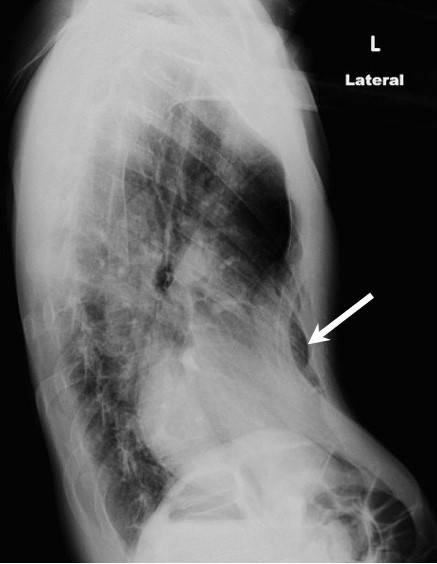

What pathology is shown?

pectus excavatum